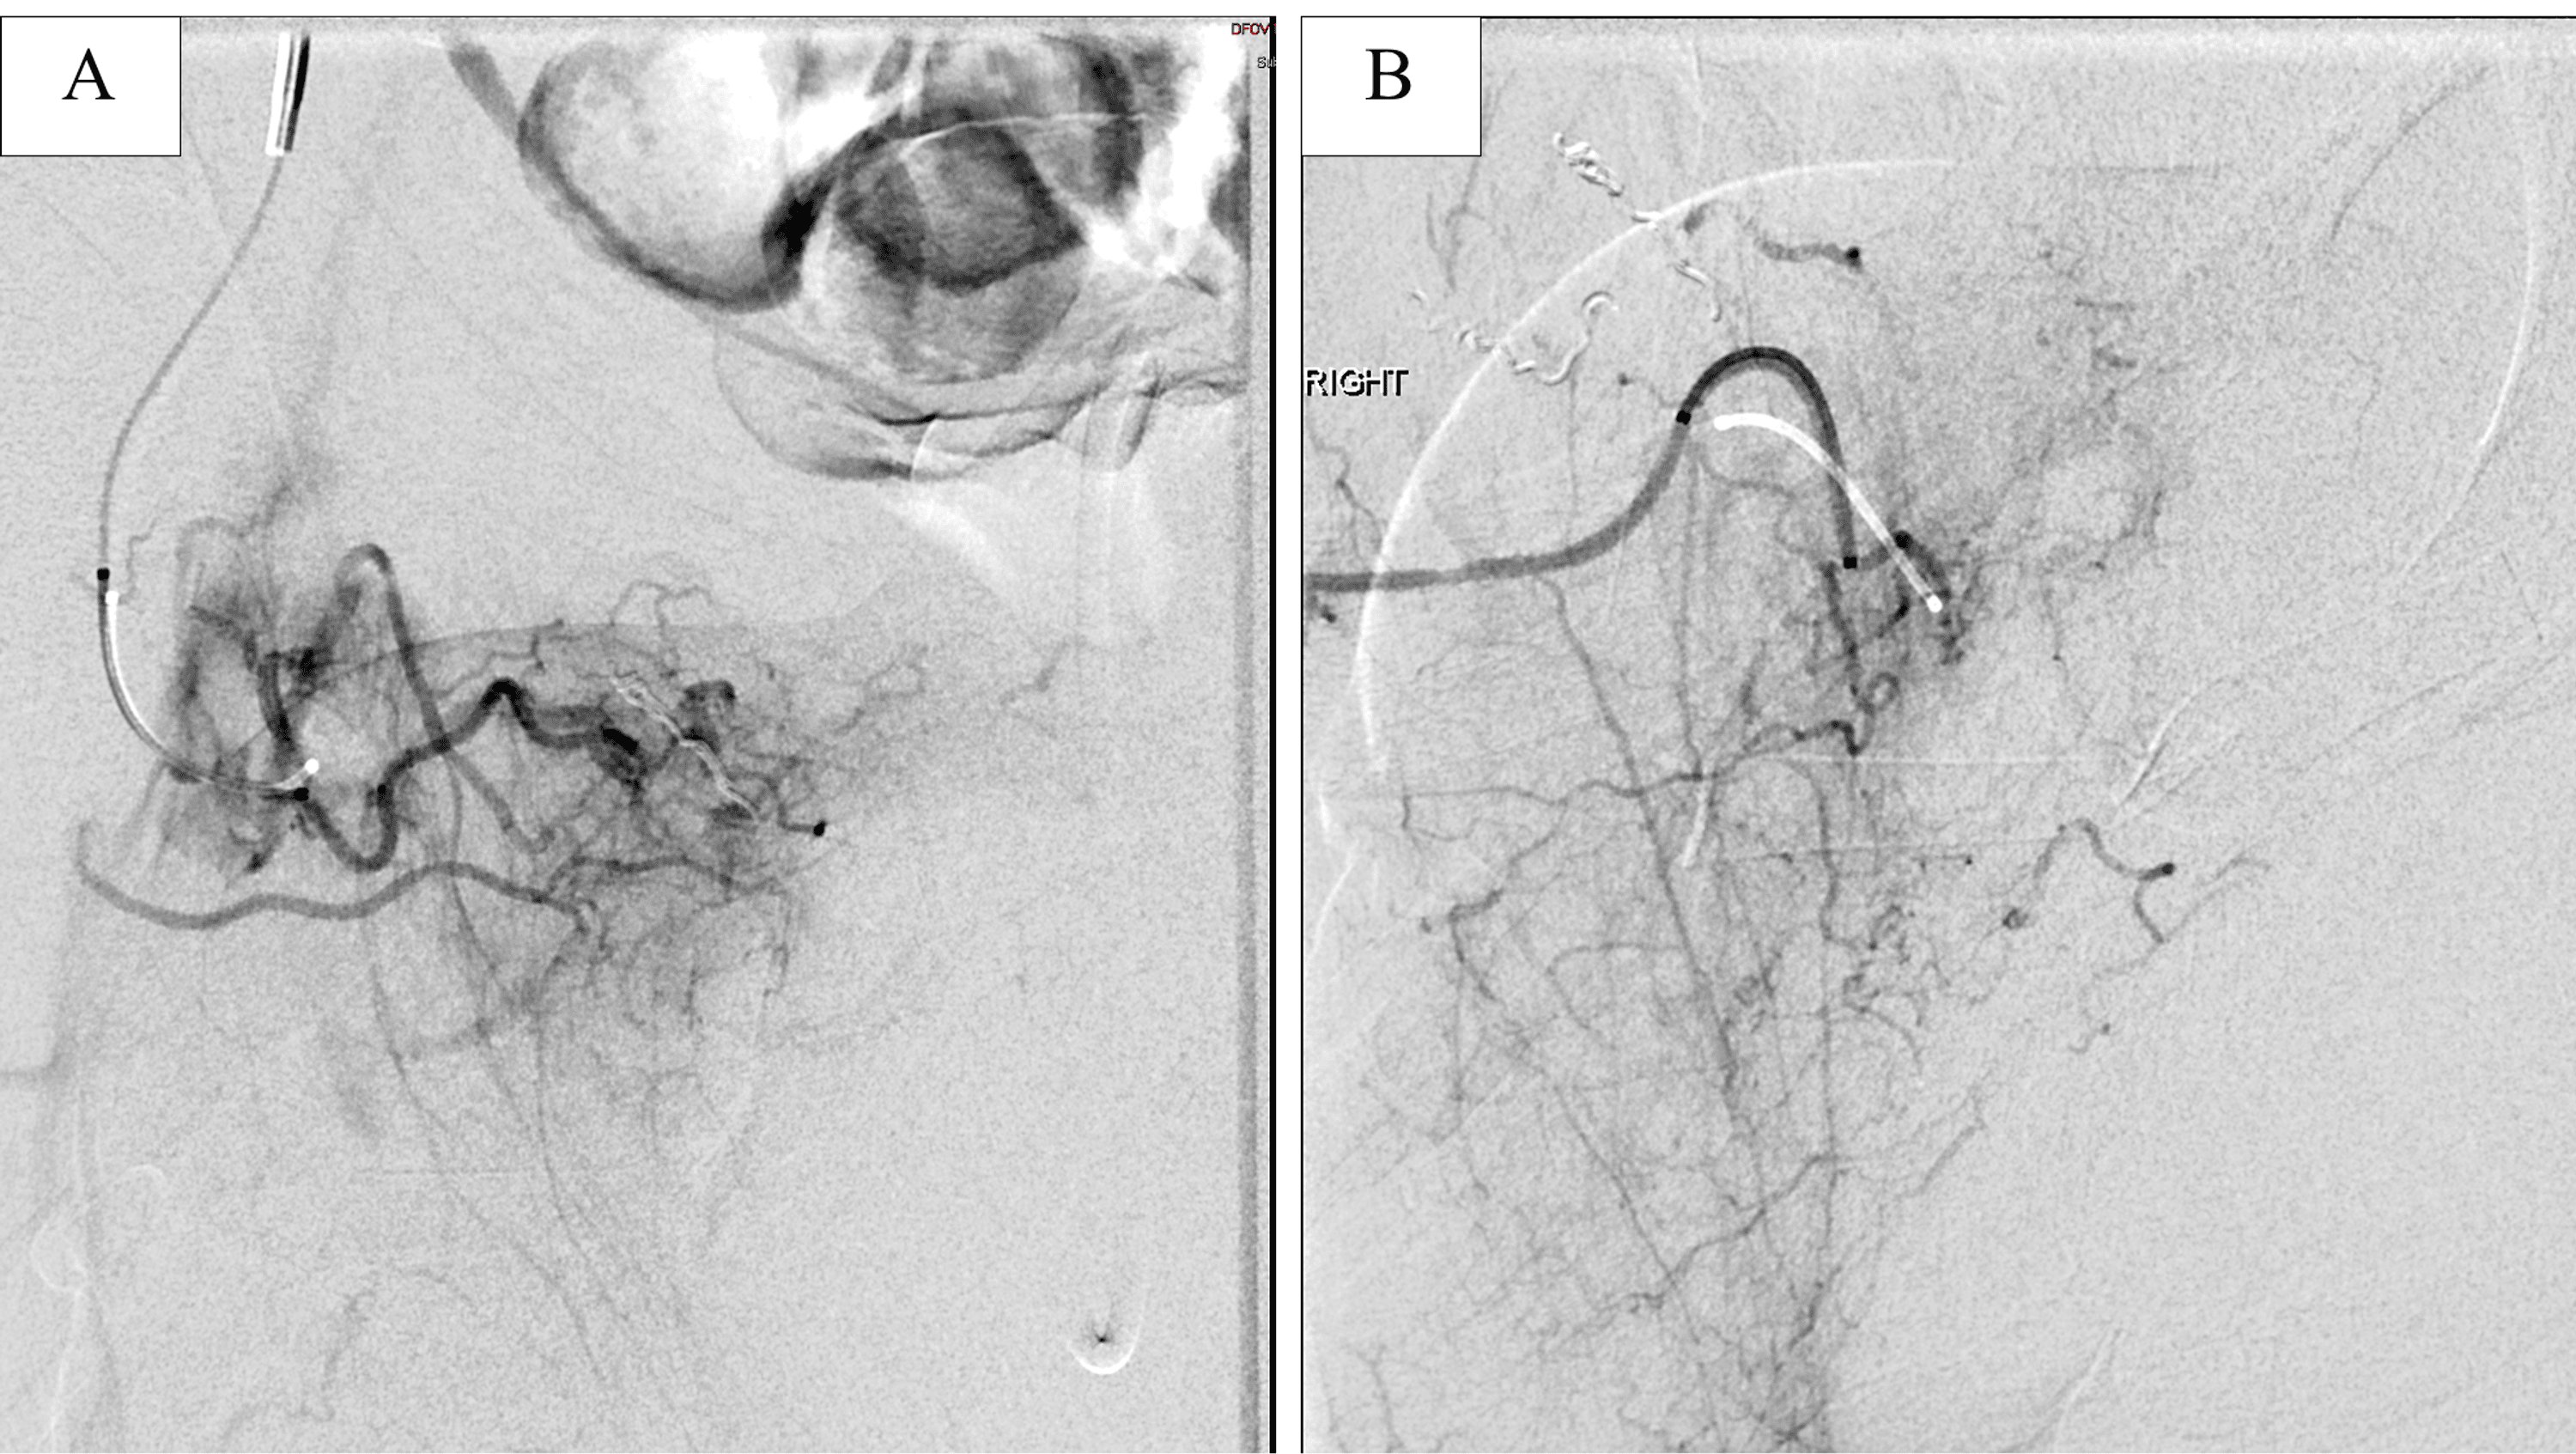

Cureus A Rare Case of Postorchidectomy Arterial Injury With Rapidly Enlarging Scrotal

From www.cureus.com

Cureus A Rare Case of Postorchidectomy Arterial Injury With Rapidly Enlarging Scrotal Coil Embolization Scrotum  It redirects blood away from an enlarged vein in your scrotum. During the procedure the doctor makes a small nick in the skin, (usually in the groin). It redirects blood away from an enlarged vein in your scrotum. Varicocele embolization is a type of medical procedure. Varicocele embolization is a type of medical procedure. Varicocele embolization is a minimally invasive. Coil Embolization Scrotum.

Cureus A Rare Case of Postorchidectomy Arterial Injury With Rapidly Enlarging Scrotal Coil Embolization Scrotum  There are several options for the treatment of varicocele, including surgical repair either by open or microsurgical approach, laparoscopy, or. Coils are commonly used embolic for varicocele, and both detachable and pushable. During the procedure the doctor makes a small nick in the skin, (usually in the groin). Varicocele embolization is an outpatient procedure with a short recovery time. It. Coil Embolization Scrotum.

Cureus A Rare Case of Postorchidectomy Arterial Injury With Rapidly Enlarging Scrotal Coil Embolization Scrotum  During the procedure the doctor makes a small nick in the skin, (usually in the groin). Varicocele embolization is a type of medical procedure. Varicocele embolization is a minimally invasive procedure which is used to treat abnormal enlargement and dysfunctional veins which. It redirects blood away from an enlarged vein in your scrotum. Varicocele embolization is an outpatient procedure with. Coil Embolization Scrotum.

Cureus A Rare Case of Postorchidectomy Arterial Injury With Rapidly Enlarging Scrotal Coil Embolization Scrotum  It redirects blood away from an enlarged vein in your scrotum. During the procedure the doctor makes a small nick in the skin, (usually in the groin). Coils are commonly used embolic for varicocele, and both detachable and pushable. It redirects blood away from an enlarged vein in your scrotum. There are several options for the treatment of varicocele, including. Coil Embolization Scrotum.

Cureus A Rare Case of Postorchidectomy Arterial Injury With Rapidly Enlarging Scrotal Coil Embolization Scrotum  Varicocele embolization is a type of medical procedure. It redirects blood away from an enlarged vein in your scrotum. Varicocele embolization is an outpatient procedure with a short recovery time. Coils are commonly used embolic for varicocele, and both detachable and pushable. It redirects blood away from an enlarged vein in your scrotum. During the procedure the doctor makes a. Coil Embolization Scrotum.

Cureus A Rare Case of Postorchidectomy Arterial Injury With Rapidly Enlarging Scrotal Coil Embolization Scrotum  During the procedure the doctor makes a small nick in the skin, (usually in the groin). Varicocele embolization is a type of medical procedure. It redirects blood away from an enlarged vein in your scrotum. Varicocele embolization is a minimally invasive procedure which is used to treat abnormal enlargement and dysfunctional veins which. There are several options for the treatment. Coil Embolization Scrotum.

Cureus A Rare Case of Postorchidectomy Arterial Injury With Rapidly Enlarging Scrotal Coil Embolization Scrotum  Varicocele embolization is a minimally invasive procedure which is used to treat abnormal enlargement and dysfunctional veins which. Coils are commonly used embolic for varicocele, and both detachable and pushable. There are several options for the treatment of varicocele, including surgical repair either by open or microsurgical approach, laparoscopy, or. During the procedure the doctor makes a small nick in. Coil Embolization Scrotum.

Cureus A Rare Case of Postorchidectomy Arterial Injury With Rapidly Enlarging Scrotal Coil Embolization Scrotum  Varicocele embolization is an outpatient procedure with a short recovery time. Coils are commonly used embolic for varicocele, and both detachable and pushable. There are several options for the treatment of varicocele, including surgical repair either by open or microsurgical approach, laparoscopy, or. During the procedure the doctor makes a small nick in the skin, (usually in the groin). It. Coil Embolization Scrotum.